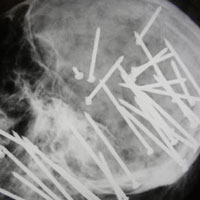

Hình ảnh cây xiên cá đâm xuyên qua hộp sọ bệnh nhân.

Theo tiết lộ, cây xiên cá dài khoảng 30 cm này đã đâm vào tận sâu hộp sọ của anh Coutinho tới 15cm.

"Khi trên đường đến bệnh viện, anh ta hoàn toàn tỉnh táo mặc dù cây xiên cá đã đâm vào mắt trái anh ta, xuyên qua hộp sọ và chỉ cách động mạch chủ vài milimet. Anh ta thật sự là một người may mắn" - Một người bạn của nạn nhân cho biết.